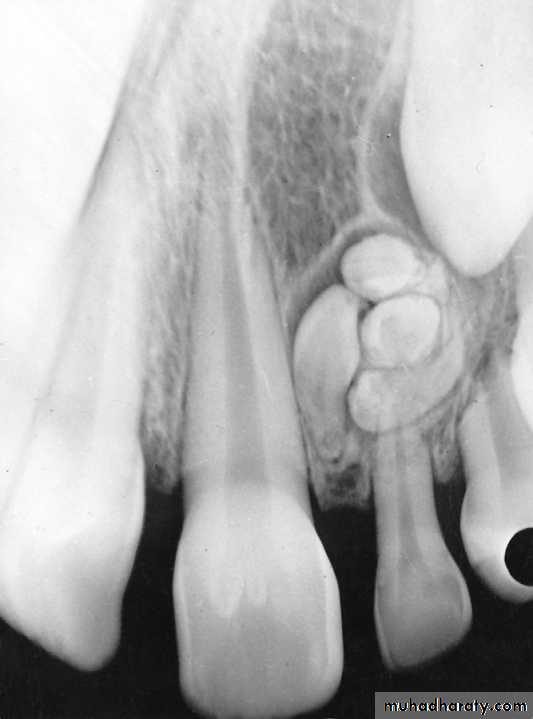

Occlusal RadiographIndications:

Determine the presence, shape and position of midline supernumerary teeth.Determine impaction of canines

Determine the presence or absence of incisors

Occlusal radiographSupernumerary tooth

Dilacerated toothPANORAMIC RADIOGRAPHY